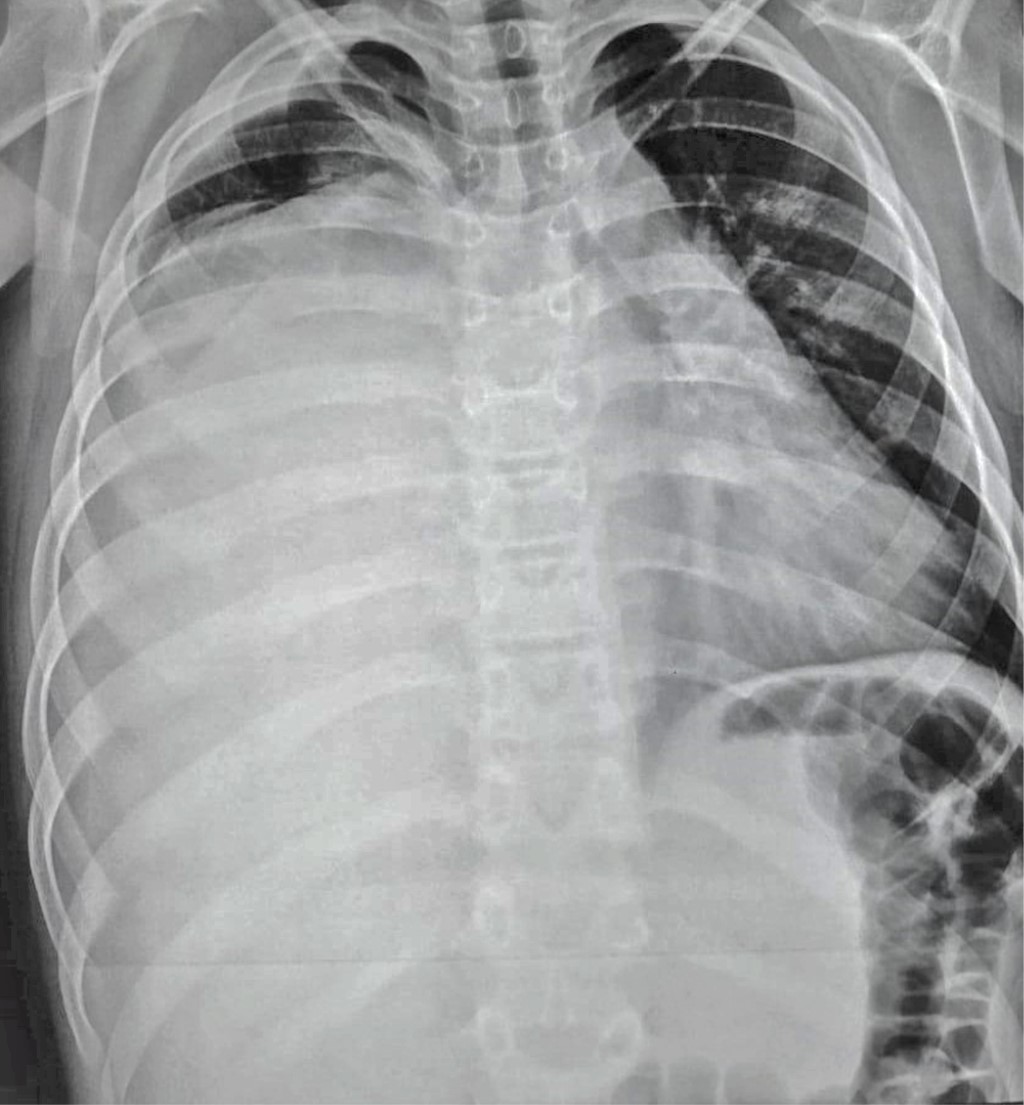

Se inicia esquema de tratamiento basado en tres ciclos de quimioterapia neoadyuvante estándar con bleomicina, etopósido y cisplatino. Los marcadores tumorales después de la quimioterapia mejoraron notablemente durante los primeros dos ciclos; sin embargo, el control radiográfico mostró un crecimiento tumoral que ocupa 80% del hemitórax derecho con aumento en el desplazamiento de las estructuras mediastinales (Figura 2). Se optó por continuar el tercer ciclo de quimioterapia, los marcadores tumorales permanecieron sin cambios, se decide realizar tomografía toracoabdominal como estudio de extensión para descartar metástasis. Lamentablemente, se evidencia un crecimiento exponencial del tumor que ocupaba 100% del hemitórax derecho y mediastino anterior sobrepasando más allá de la línea media del cuerpo con colapso del pulmón derecho, desplazamiento del corazón y grandes vasos hacia el lado izquierdo así como los componentes del mediastino posterior como tráquea y esófago, el abdomen sin evidencia de metástasis (Figura 3). Se realizó ecocardiograma transtorácico con datos de disfunción diastólica del ventrículo derecho con compresión de la aurícula derecha y vena cava inferior, hipertensión arterial pulmonar moderada, levocardia, levoapex, desplazamiento extremo del corazón a la línea axilar media, lo que implicaba empeoramiento clínico de nuestro paciente.